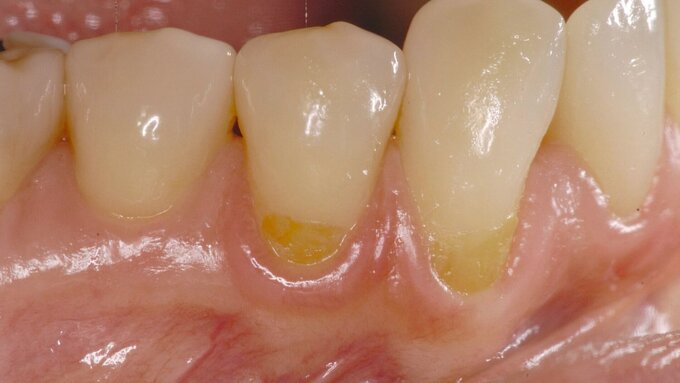

Parodontitis

... ist eine häufige chronische Entzündungserkrankung des Menschen, die durch die Zerstörung des Zahnhalteapparats aufgrund von Entzündungsreaktionen definiert ist und zu Zahnverlust führen kann. Parodontitis wird durch den pathologischen dentalen Plaque-Biofilm oberhalb und unterhalb des Zahnfleischs initiiert.